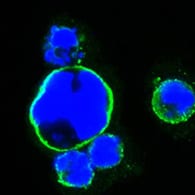

分类: 科研抗体货号: 20345别名: Isl-1; ISLET1应用: IHC,IF反应种属: Human,Mouse,Rat,Rabbit

分类: 科研抗体货号: 20344别名: Isl-1; ISLET1应用: IHC,IF反应种属: Human,Mouse,Rat,Rabbit